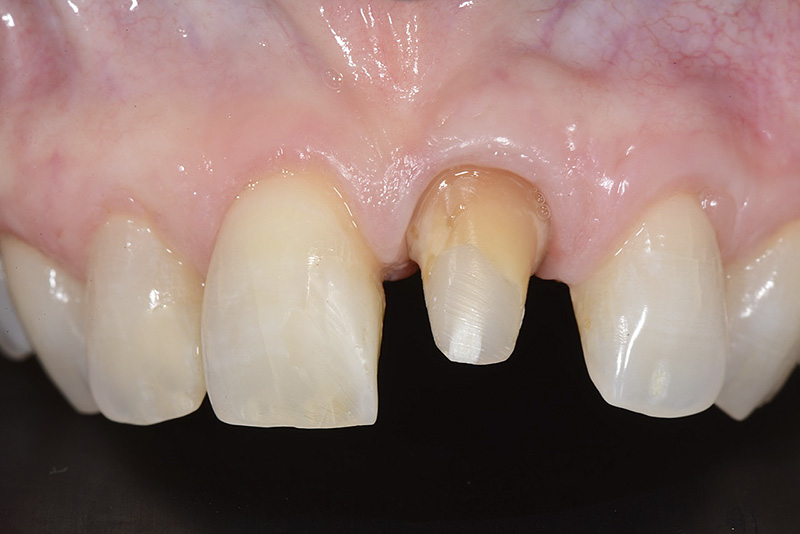

Vengono utilizzati 2 tipi di provvisori: il primo, cementato ai denti vicini, viene utilizzato dal momento dell’estrazione del dente fino ad impianto osteointegrato (circa 6 mesi); il secondo, avvitato direttamente all’impianto, ha una funzione di prova estetica ma soprattutto di guida per la maturazione dei tessuti gengivali peri-implantari portandoli verso la maturazione completa prima di posizionare la corona finale in disilicato di litio.